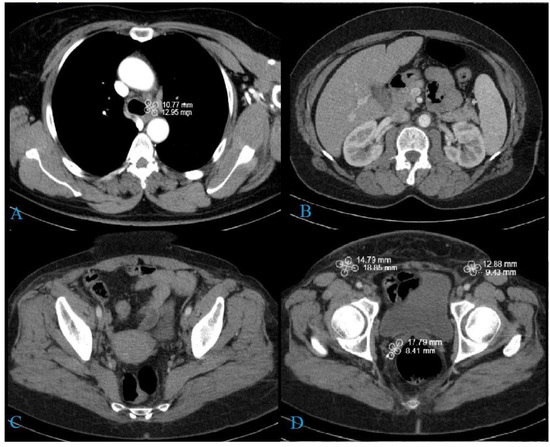

2. Case Report